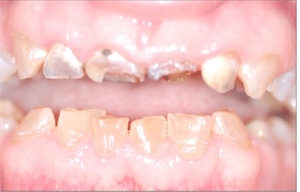

The affected teeth appear gray to yellowish brown and have broad crowns and

constricted root giving it an appearnce of tulip shape.

The teeth appear blue - gray or amber colored.

They can be distinguished from Type-1 due to the presence of multiple pulp exposures, non mineralized pulp chambers and presence of shell teeth.